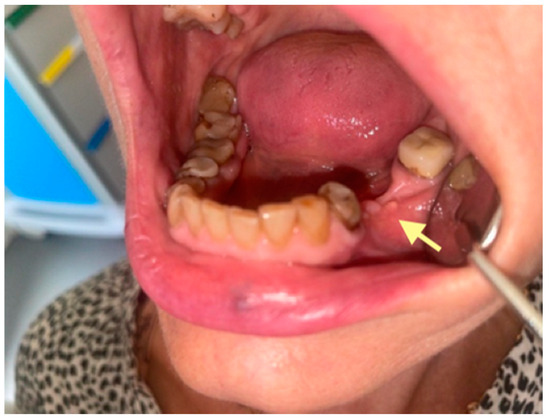

2.3. The Third Case (See Table 1)

The third patient was a 75-year-old female with osteonecrosis of the mandible and maxilla in the fourth and in the second quadrant (see Figure 7, Figure 8 and Figure 9). The patient had third-stage jaw osteonecrosis. In 2023, the patient was diagnosed with osteonecrosis of the upper and lower jaw caused by antiresorptive therapy (until August 2021, the patient regularly used Zolendronic acid; then, this drug was replaced by the RANKL inhibitor Denosumab). The treatment was periodically complicated by submandibular and submental abscesses. In addition, due to the progression of the underlying disease, constant courses in chemotherapy were administered. The patient underwent three operations, which included sequestrectomy of the jaw with simultaneous use of A-PRF, antrotomy with revision of the maxillary sinus, closure of the oroantral communication, and opening and revision of abscesses of the soft tissues (see Figure 10 and Figure 11)

Figure 10.

CT of the head and facial bones (19 March 2025) before the last operation (sequestrectomy of the lower and upper jaws; antrotomy performed).

Figure 11.

The photos show the patient 2 months after the last operation (sequestrectomy of the lower and upper jaws; antrotomy and A-PRF application). The healing of the surgical wounds is incomplete, but there is a positive tendency towards healing.